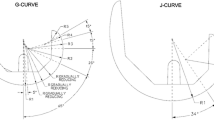

Here, we propose an explanation for this mechanism under weight-bearing conditions (Fig. 4). Standard gravity produces a posterior force on the femur through PTS and locates the femur posteriorly to some extent. A CR TKA does not contain an ACL, and therefore, the prosthesis cannot positively resist this posterior force, and the femur moves posteriorly to the equilibrium position (Fig. 4b). Regarding the medial condyle in varus alignment, large weight loading generates a large posterior force, and the femur is forced to locate posteriorly to maintain its equilibrium position (Fig. 4c). Regarding the lateral condyle in varus alignment, little weight loading generates little posterior force on the femur (Fig. 4a).

Posterior translation force on the femur generated by weight load and the posterior tibial slope. a A small weight load generates a small posterior force on the femur, and the femur is translated anteriorly relative to the tibia (The lateral condyle of the varus alignment group). b A standard weight load generates posterior force on the femur, and the femur is located in it normal position relative to the tibia. c A large weight load produces a large posterior force, and the femur is translated posteriorly relative to the tibia. (The medial condyle of the varus alignment group)